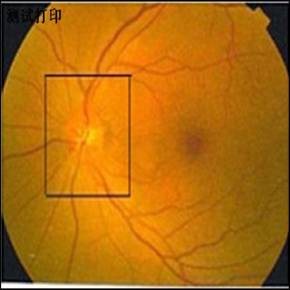

眼底图像检验系统是引入了现代技术,计算机系统集成和成像系统的结合,使其具有多功能的仪器,如存档(拍摄),打印,查询,统计等,并配上计算机操作软件和病例软件。

其独创性在与仪器可使用于免散瞳的这一功能,使许多不能散瞳的疾病得到检查,并带有图形,大大提高了眼底图像的使用范围,从而扩展疾病的检验范围,提高医院的疾病医疗质量,为提高人民健康水平做出贡献。

眼底图谱更是一种研究、诊断的重要资料。因此,眼底图像检验系统的临床适用范围广:适用于眼科疾病、青光眼、心血管科高血管科高血压糖尿病等;内外科,脑神经内外科,妇产科的妊高症,都可以借助眼底状况检查诊断疾病以及疾病进展程度,在当前我国人均寿命日益提高,老龄群体日益扩大的情况下,眼底图像检验系统的问世为提高我国人民的身体健康水平、生存质量,为医疗系统开辟了一条崭新的眼底图像诊病道路